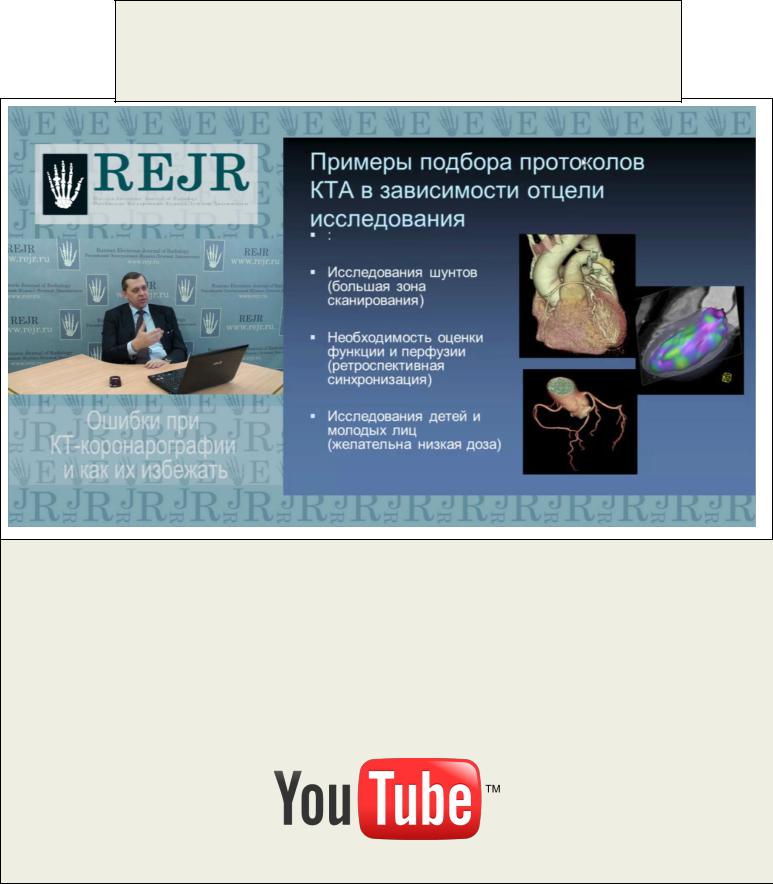

МАСТЕР-КЛАСС

ОШИБКИ ПРИ КТ-КОРОНАРОГРАФИИ И КАК ИХ ИЗБЕЖАТЬ

Синицын В.Е.

Всем нам известно, какого уровня развития достигла компьютерная томография и, в частности, КТ-коронарография в последние годы. Расцвет КТ-ангиографии открыл новую эру в диагностике болезней сердца и сосудов. Количество прово-

димых КТ-коронарографий во всем мире растет с каждым годом. В то же время, каждый метод обладает своими ограничениями, а объем диагностической информации может создавать трудности в еѐ интерпретации даже у опытного специалиста. Какие основные диагностические ошибки при КТ-коронарографии? Как их избежать? Об этом и будет вестись речь в сегодняшнем мастер-классе.

Для просмотра мастер-класса перейдите на сайт: http://rejr.ru/devyatyi_nomer/master-class.html

Мастер-класс. ОШИБКИ ПРИ КТ-КОРОНАРОГРАФИИ И КАК ИХ ИЗБЕЖАТЬ